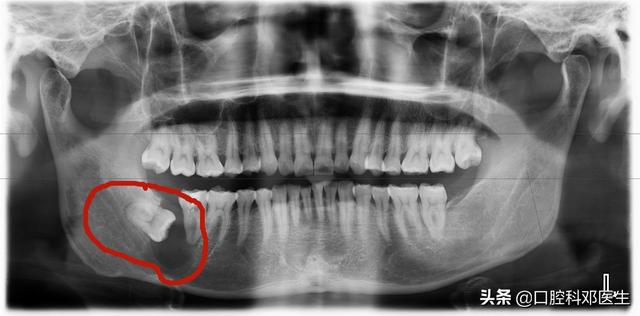

3.引起肿瘤或囊肿的智齿

由于智齿阻生,智齿无法萌出,最后引起了囊肿或者肿瘤,这个是需要手术,同时也是需要拔掉智齿的!